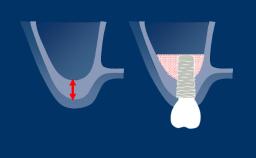

Introduction to Implant Dentistry

Post-Extraction Ridge Alteration - A Risk for Esthetics

Congress Lecture

Introduction to Implant Dentistry

Healing of the Extraction Socket

Learning Module